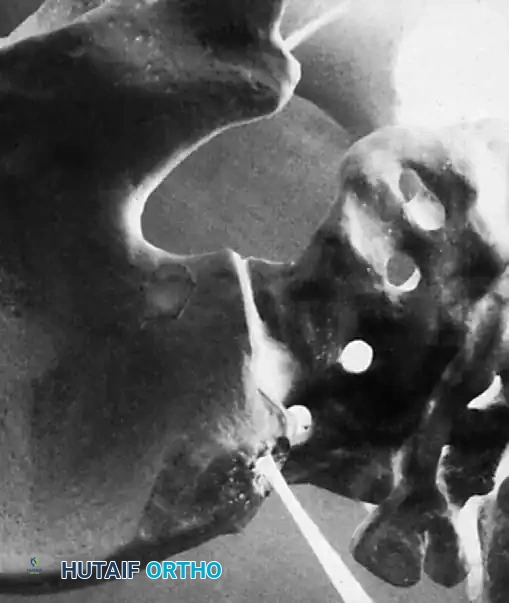

Associated Surgical & Radiographic Imaging

Hutaifortho's Orthopaedic Diagram